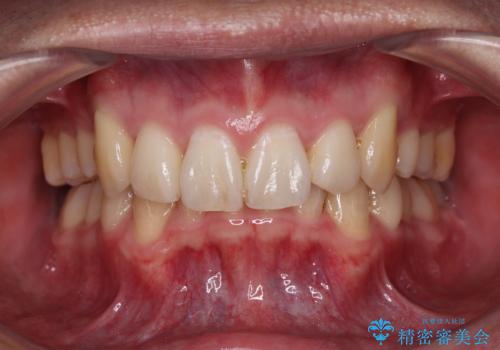

[ マウスピース矯正 ] がたがたした歯並びを治したい

担当医 大元洋佑

![[ マウスピース矯正 ] がたがたした歯並びを治したいの症例 治療前](https://seimitsushinbi.jp/wp/wp-content/uploads/2024/04/IMG_0106-500x350.jpg?v=1711951424)

![[ マウスピース矯正 ] がたがたした歯並びを治したいの症例 治療後](https://seimitsushinbi.jp/wp/wp-content/uploads/2024/04/46939b7482334672d3a091da1562afec-500x350.jpg?v=1711951403)